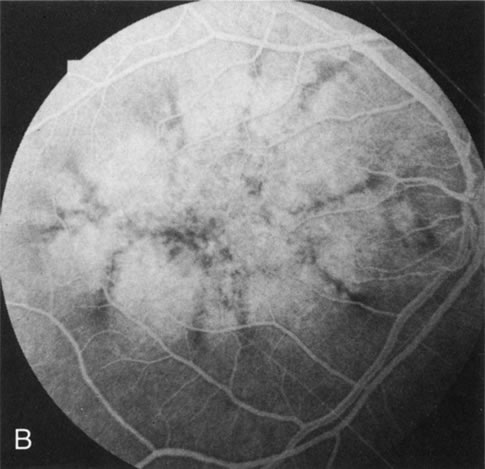

In retinitis pigmentosa (RP), the pigment abnormalities of atrophy, migration, and clumping are made apparent by transmitted hyperfluorescence and blocked hypofluorescence (Fig. 1A). Patients who have very minimal pigmentary alterations (pauci pigmentary RP) or no pigment abnormalities (RP sine pigmento) may show the abnormalities on fluorescien angiography (FA). It is uncommon to see choriocapillaris atrophy except in the late stages. This finding corresponds to the histopathology, which shows that the earliest abnormalities are in the photoreceptors and that the choroid is normal.1

Fig. 1. Retinitis pigmentosa. A. A typical area of bone spicule pigmentation. B. Diffuse dye leakage is apparent throughout the posterior pole. C. The early angiogram shows dilated and irregular retinal radial peripapillary capillaries and perifoveal retinal capillaries. D. Leakage from these vessels are evident in the late angiogram.

Dye leakage in RP may occur from the retinal vessels or at the level of the retinal pigment epithelium (Fig. 1B).2–4 The leakage may be seen in the macula and posterior pole, along the vascular arcades in the distribution of the radial peripapillary capillaries, and in the periphery (where an exudative vasculopathy resembling Coats' disease is suggested).

Of more clinical importance is the role of FA in the diagnosis and treatment of cystoid macular edema (CME) (Fig. 1C and D). Stereoscopic FA indicates that the leakage, which may be diffuse or have the typical petaloid stellate appearance of CME, can come from the perifoveal retinal capillaries, from the choroid through the RPE, or from a combination of both sources.4 With the recent suggestion that CME in RP may be successfully treated with acetazolamide,5, 6 FA is thus important to document the diagnosis of CME, establish the origin(s) of leakage, and follow patients during and after therapy.